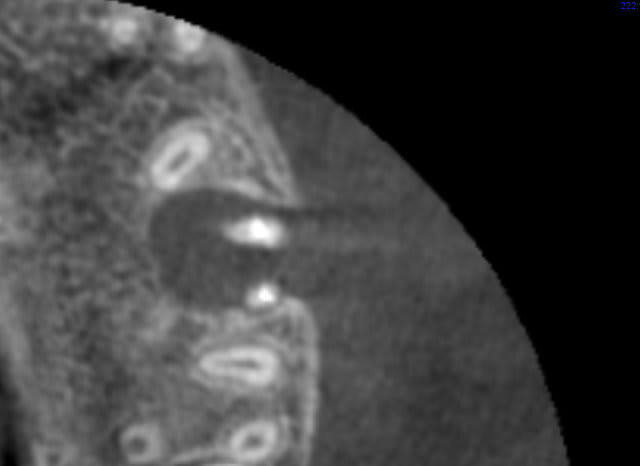

Ok, donc 2 autres coupes axiales:

Mais au bout d'un moment la 3 d montre pas tout: tu peux ne pas voir une lumiere canalaire qui existe dans la dent.

+ l'artefact du gros cone de gutta

(j'ai mis 2 fois la meme : arrive pas à la retirer)

sur la 4ème coupe, on voit que l'endo du canal palatin n'est pas top. tu as repris tous les canaux ou uniquement les mvs?

ah non, j'ai tout repris bien évidemment.

Et comme c'est tout large verifié qu'il reste plus de gutta/cracra collés aux parois. + irrig activée par laser (cherry on the top)